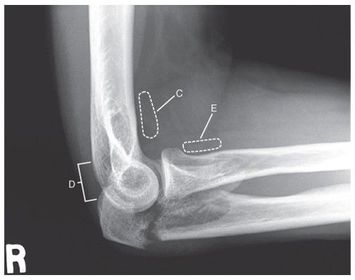

C. anterior fat pad D. posterior fat pad E. supinator fat stripe (not visible)

Which fat pad of the elbow will only appear on x-ray if there's a joint pathologic process? Posterior Fat Pad

Why does the elbow need to be in 90 degree flexion to determine whether the posterior fat pad is visible or not? When elbow is flexed more or less than 90 degrees it pushes the fat pad into different position, it can show up on x-ray then when there's no pathologic issue